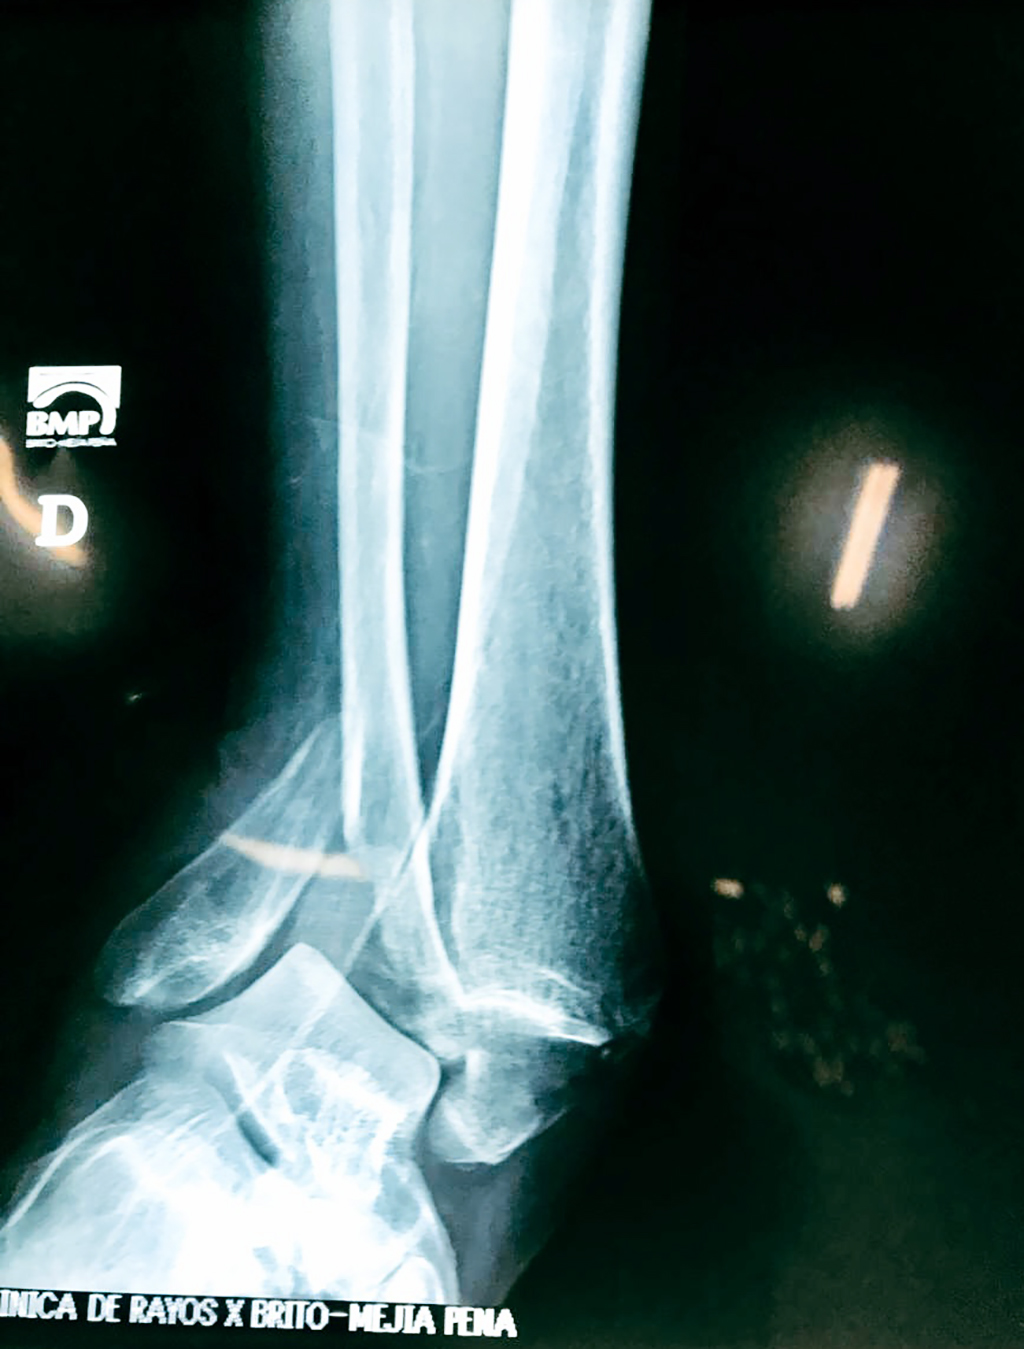

Una fractura de tobillo es la rotura de uno o más de los huesos del tobillo. Estas fracturas pueden ser:

- Parciales (el hueso está sólo parcialmente fisurado, no del todo).

- Completas (el hueso está perforado y está en 2 partes).

- Producirse en uno o ambos lados del tobillo.

Algunas fracturas de tobillo pueden requerir cirugía si:

- Los extremos de los huesos están desalineados entre sí (desplazados).

- La fractura se extiende hasta la articulación del tobillo (fractura intra-articular).

- Los tendones o ligamentos (tejidos que sujetan los músculos y los huesos entre sí) están rotos.

Cuando se necesita cirugía, es probable que esta implique el uso de clavijas de metal, tornillos o placas para sostener los huesos en su lugar mientras la fractura se consolida. Los elementos de soporte pueden ser temporales o permanentes.